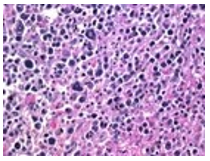

Figure 1 Hepatosplenic T cell lymphoma comprised of neoplastic cells demonstrating miniature to medium cells imbued with pale, a-granular cytoplasm, elliptical nuclei, condensed nuclear chromatin, inconspicuous nucleoli admixed with numerous blasts [4,5].

Figure 2 Hepatosplenic T cell lymphoma depicting miniature to intermediate neoplastic lymphocytes incorporated with pale cytoplasm with absent granules, elliptical nuclei, condensed chromatin and inconspicuous nucleoli [4,5].

Cytological examination exhibits variable, cellular smears comprised of monotonous, miniature to intermediate cells incorporated with pale, a-granular cytoplasm, spherical to elliptical nuclei, moderately condensed nuclear chromatin and inconspicuous nucleoli [3,.4].

Cellular blasts appear as intermediate to enlarged cells with enhanced nucleo- cytoplasmic ratio, finely dispersed nuclear chromatin and absent nucleoli.